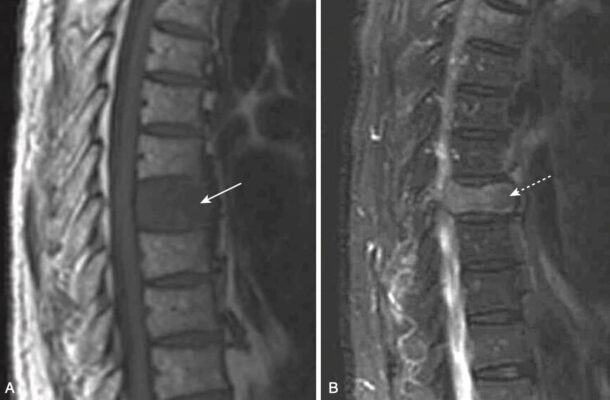

- MRI có thể phát hiện những thay đổi của di căn cột sống thậm chí sớm hơn so với quét phóng xạ hạt nhân, và kỹ thuật hiện nay có thể cho phép sàng lọc nhanh toàn bộ cơ thể tương tự như quét xương bằng phóng xạ hạt nhân.

- Với thâm nhiễm tân sinh của tủy xương, có sự giảm tín hiệu bình thường cao của đốt sống trên các hình ảnh T1W, và thường có tín hiệu cao trên các hình ảnh T2W (Hình 14).

- Không giống như gãy xương do nén do loãng xương (có xu hướng không ảnh hưởng phần sau của thân đốt sống trong khi làm xẹp phần trước và giữa), di căn cột sống thường ảnh hưởng đến toàn bộ thân đốt sống, bao gồm cả phần sau.